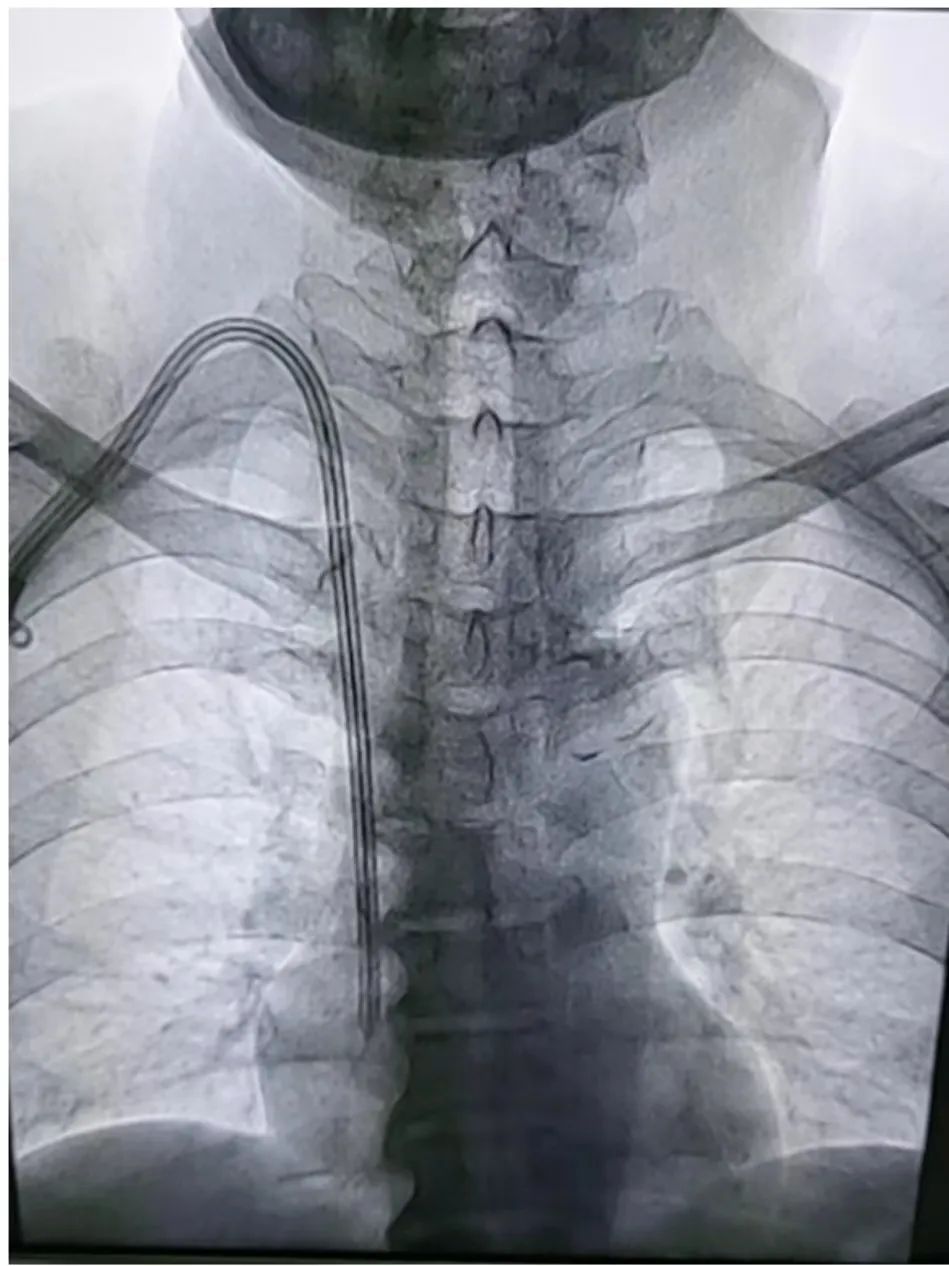

我院肾病科成功开展首例DSA(数字减影血管造影术)下带隧道和涤纶套的透析导管更换术

介入技术也成为该领域的重要保障措施。与传统置管相比,介入下置管更为安全精准及可视化,导丝精准进入,减少血管损伤及防止误入分支静脉,对血管基础较差,血管狭窄等血管条件复杂情况的治疗,具有得天独厚的优势,是未来发展重要方向之一。